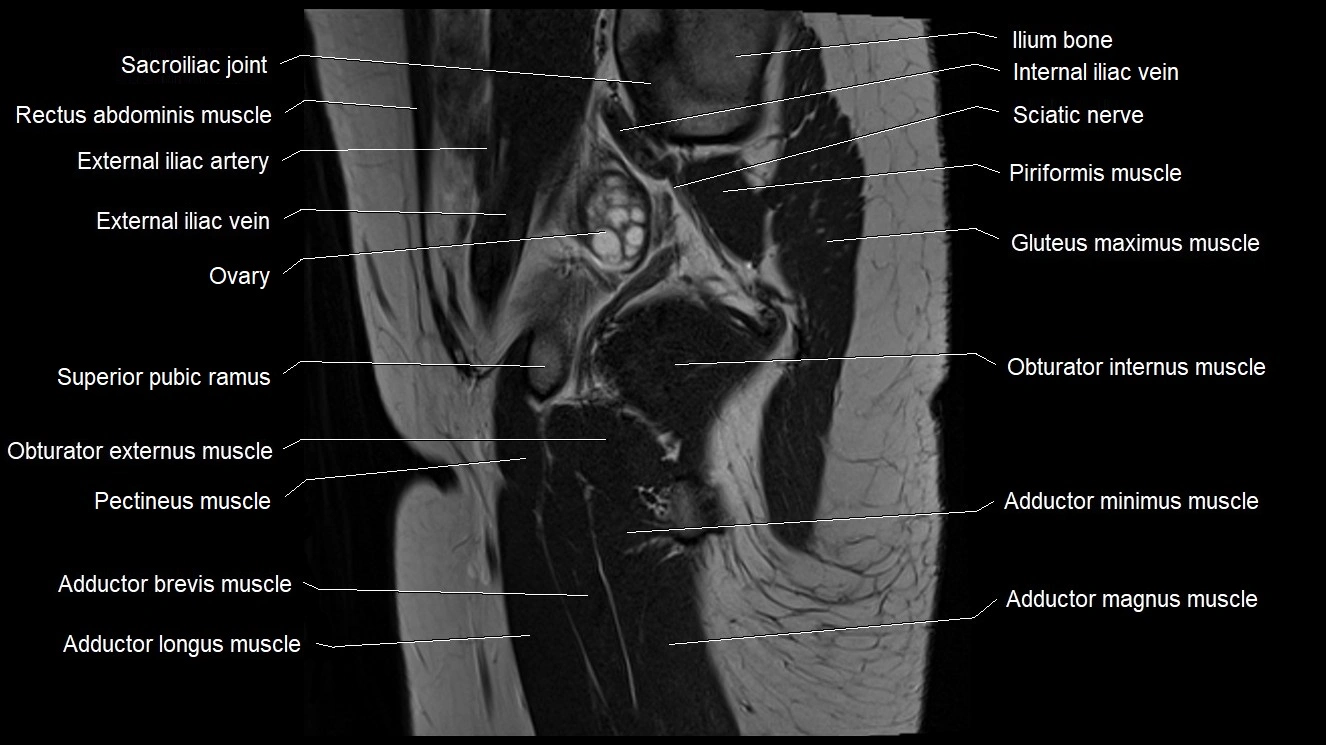

- Adductor brevis muscle

- Adductor longus muscle

- Adductor magnus muscle

- Adductor minimus muscle

- Gluteus maximus muscle

- Ilium bone

- Obturator internus muscle

- Pectineus muscle

- Superior pubic ramus